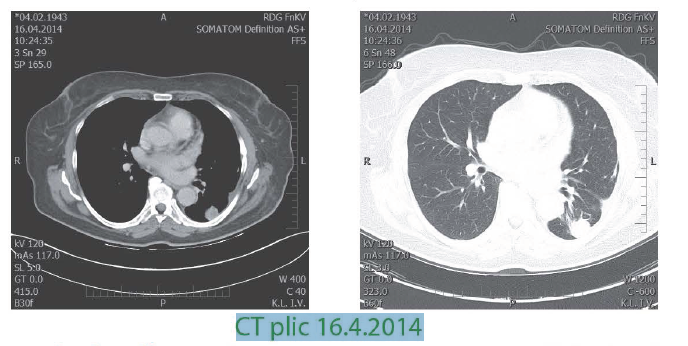

II. meta do plic

- 12/2013 pro susp. pneumonii, bolesti na hrudi a nejasný nález na rtg plic - provedeno diagnostické CT hrudníku: susp. meta dolního plicního laloku a sousední pleury vlevo, opět bez nálezu další generalizace, MRI mozku - reziduum tumoru neprokázáno; 3/2/2014-WATTS I.sin s odstraněním metastázy, histologicky- meta maligního melanomu levé plíce, resekát pleury bez maligních struktur, RO resekce, indikována k dispenzarizaci